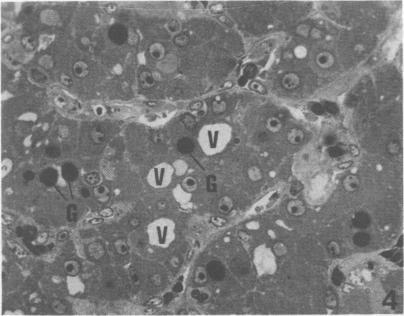

Twenty-five large broad-breasted white turkeys were fed a 22% protein diet supplemented with 500 ppm furazolidone from day 1 to 3.5 weeks of age and the same diet supplemented with 700 ppm furazolidone until 9.5 weeks of age. Following the development of round heart disease as indicated by altered electrocardiograms the 25 turkeys were sacrificed. In the livers of turkeys with biventricular dilatation (72% of cases) there was bile duct hyperlasia, portal fibrosis and intracytoplasmic globules in the hepatocytes. Globules stained pink with hematoxylin-eosin, deep red with PAS and variable with Massons trichrome stains in paraffin-embedded liver sections. Clear intracytoplasmic vacuoles demonstrable in hepatocytes of PAS stained liver sections embedded in paraffin did not stain as lipid in frozen sections but did contain sparse flocculent material in 1 micrometer sections of liver embedded in epoxy resin and stained with toluidine blue. At the subcellular level, the intracytoplasmic globules in hepatocytes were surrounded by a single membrane, contained flocculent material and had enzymatic properties characteristic of lysosomes. Blood pressure, heart rate, dp/dt max, total plasma proteins and plasma trypsin inhibitory capacity of turkeys with round heart disease were lower than corresponding values for control turkeys. Control turkeys did not exhibit the characteristic gross or microscopic lesions of round heart disease.

25只大型宽胸白火鸡在1至3.5周龄时喂食含22%蛋白质且添加500 ppm呋喃唑酮的日粮,在9.5周龄前喂食相同日粮但添加700 ppm呋喃唑酮。在心电图出现改变表明出现圆心病后,将这25只火鸡宰杀。在双心室扩张的火鸡肝脏中(72%的病例),出现了胆管增生、门脉纤维化以及肝细胞内的胞质内小球。在石蜡包埋的肝脏切片中,小球苏木精-伊红染色呈粉红色,PAS染色呈深红色,Masson三色染色则呈不同颜色。在石蜡包埋的PAS染色肝脏切片的肝细胞中可看到的透明胞质空泡,在冰冻切片中不被染成脂质,但在环氧树脂包埋并用甲苯胺蓝染色的1微米肝脏切片中确实含有稀疏的絮状物质。在亚细胞水平,肝细胞内的胞质内小球被单层膜包围,含有絮状物质,并具有溶酶体的酶学特性。患有圆心病的火鸡的血压、心率、dp/dt max、总血浆蛋白和血浆胰蛋白酶抑制能力均低于对照火鸡的相应值。对照火鸡未表现出圆心病的典型大体或微观病变。